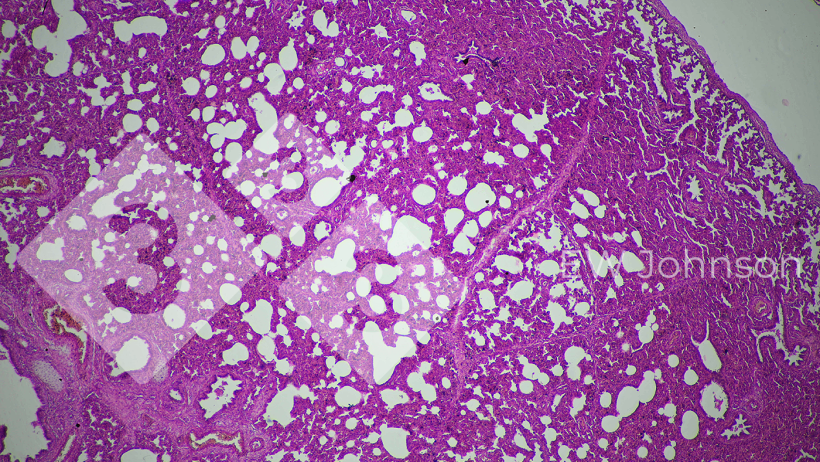

A PCR foi negativa para PRRS, pseudo-raiva (doença de Aujeszky), circovírus suíno PCV2 e PCV3, peste suína clássica (PSC) e peste suína africana (PSA). A granja era conhecida como livre de PRRS, Aujeszky, Circovirose e PSA antes deste evento. A PCR para Getahvirus em pulmão de leitão foi altamente positiva. A histopatologia revelou pneumonia intersticial grave (Figura 3) e meningoencefalite fibrino-hemorrágica (Figura 4). Foi diagnosticada doença perinatal por Getahvirus. A granja foi informada de que esta doença é transmitida principalmente por mosquitos e medidas de controle foram aplicadas. Não houve mais casos ou sinais clínicos na granja e a produção voltou ao normal.